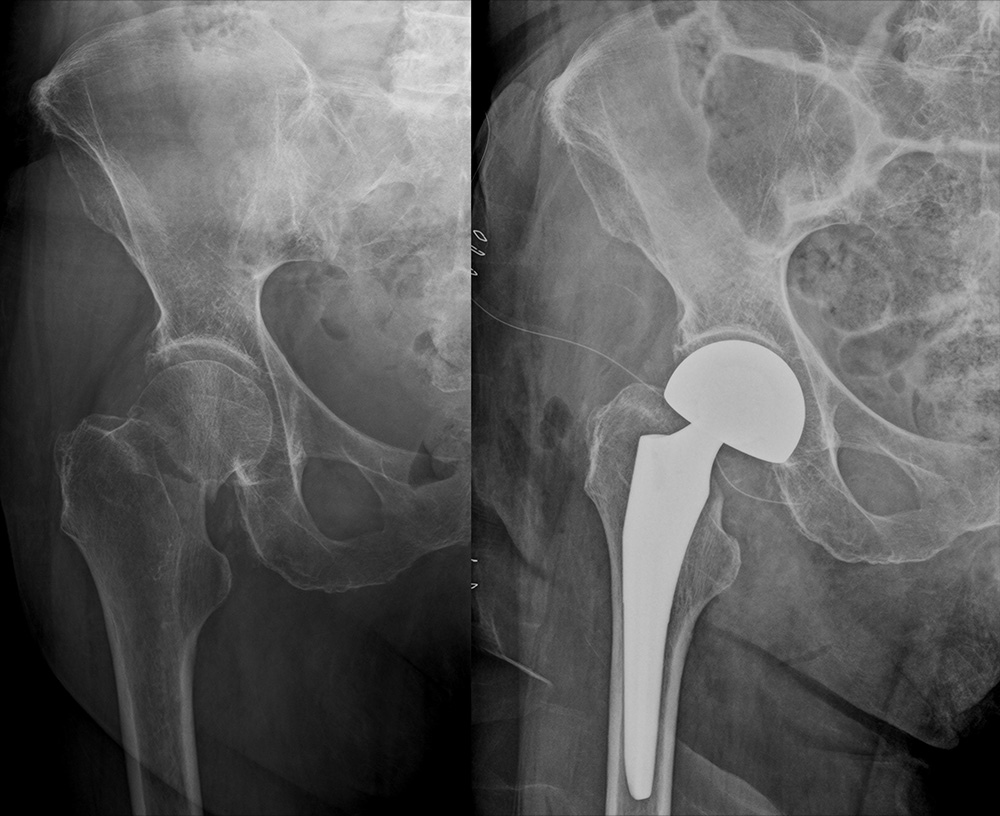

高齢者の方々によく起こる大腿骨頚部骨折(図1・図2)、肩から上腕の骨折(図3)、手関節周囲の骨折(図4)、人工膝関節置換術(図5)などの手術を行っております。

人工骨頭挿入術

図1:人工骨頭挿入術